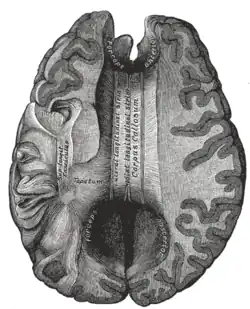

![]() Sagittal section of brain, front part to the left. The corpus callosum can be seen in the center, in light gray | |

The corpus callosum (Latin for "tough body"), also callosal commissure, is a wide, thick nerve tract, consisting of a flat bundle of commissural fibers, beneath the cerebral cortex in the brain. The corpus callosum is only found in placental mammals.[1] It spans part of the longitudinal fissure, connecting the left and right cerebral hemispheres, enabling communication between them. It is the largest white matter structure in the human brain, about 10 in (250 mm) in length and consisting of 200–300 million axonal projections.[2][3]

The corpus callosum forms the floor of the longitudinal fissure that separates the two cerebral hemispheres. Part of the corpus callosum forms the roof of the lateral ventricles.[5]

The corpus callosum has four main parts – individual nerve tracts that connect different parts of the hemispheres. These are the rostrum, the genu, the trunk or body, and the splenium.[4] A narrowed part between the trunk and the splenium is known as the isthmus. Fibres from the trunk and the splenium known together as the tapetum form the roof of each lateral ventricle.[6]